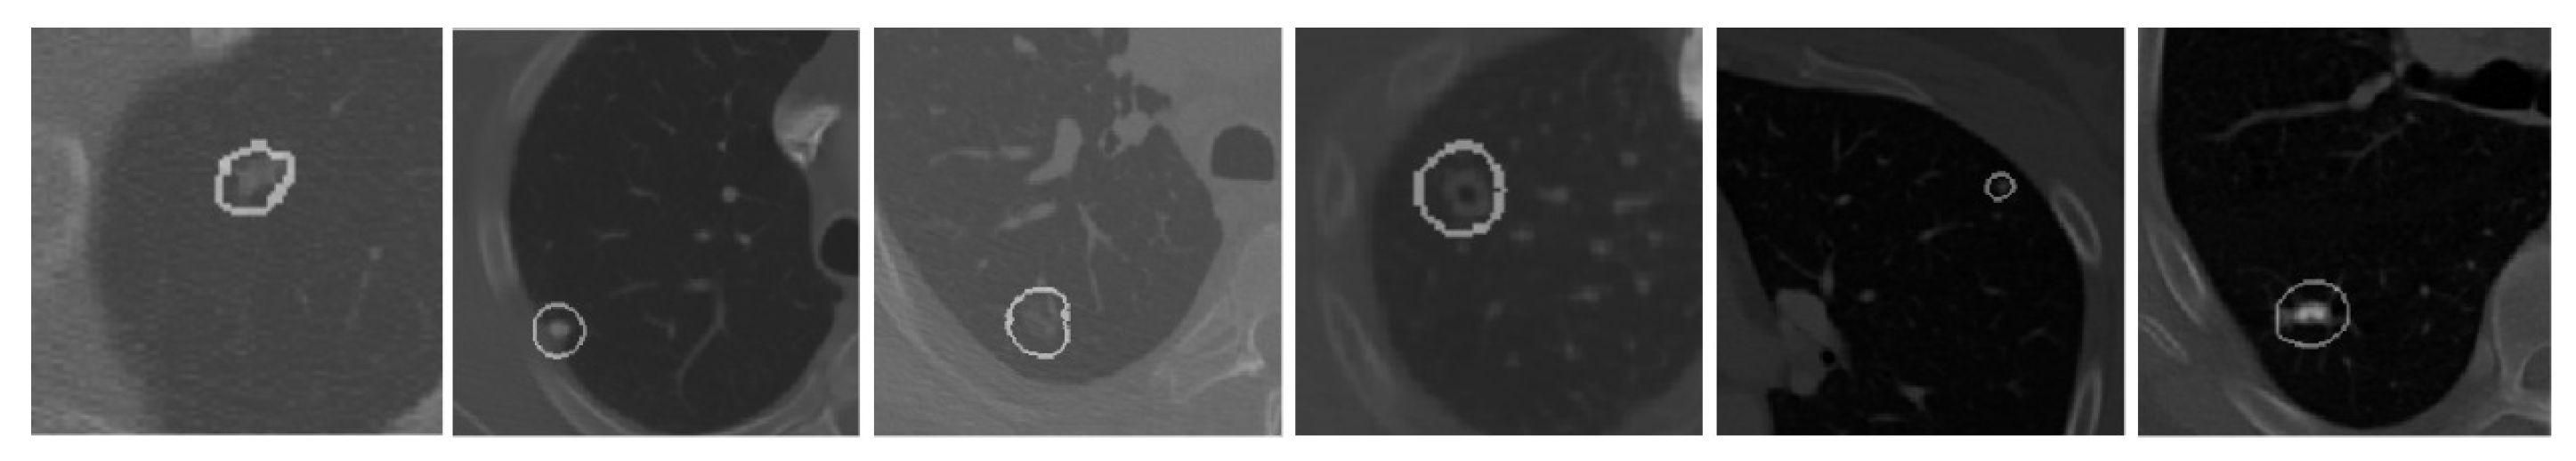

The segmentation results of complex cases, including attached (juxtapleural and juxta-vascular) and small-size nodules from both the LUNA16 and QIN Lung CT datasets, are shown in Figure 6. On observation of the results, it becomes apparent that the U-Det model outperforms the ground truth labels indicating the generalization potential of the model. The mean DSC outcomes on various lung nodule types from both datasets are shown in Table 4 and Table 5. By examining the experimental data shown in Table 4 and Table 5, it can be observed that the U-Det model’s potential for robust segmentation does not depend upon the type of nodule as it has shown exceptional performance on even small-size nodules.

Figure 6.

Qualitative depiction representing the ground truth masks and segmentation results of the U-Det model. Here, figures (a–c) are from the LUNA16 dataset, and (d–f) are from the QIN Lung CT Segmentation dataset. Note: The red filter represents the ground truth mask, and the blue filter represents the segmentation results.